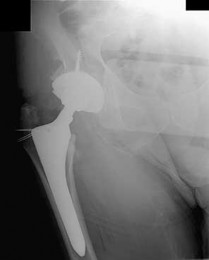

What is the most likely explanation for the change between the initial intraoperative radiograph (Figure 11a) and the radiograph taken 4 weeks after surgery (Figure 11b) in an 87-year-old man who underwent primary hip replacement for osteoarthritis?

The image demonstrates subsidence of the femoral implant. The implant subsided because it did not have good initial stability. The tapered femoral implant was placed after initial preparation for an anatomic femoral stem. A limited, nondisplaced femoral neck fracture was encountered during the procedure and treated. Two advantages of tapered stems are the efficient transfer of stress to the proximal femur and the ability to accommodate some subsidence to achieve enhanced stability. Although subsidence of a tapered stem to a more stable position can produce a good result, quality of metaphyseal bone should be considered. Attention to surgical technique remains important to optimize component stability for biological fixation.